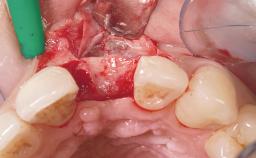

Late Flapless Placement of an Implant in a Maxillary Left Central Incisor Site

A 39-year-old male patient presented with a chief complaint of discomfort and gingival discoloration around his maxillary left central incisor. He was in good general health and was a non-smoker. His past dental history was significant because of the traumatic fracture of tooth 21 in a sporting accident at age 13. Initial dental treatment included endodontic therapy and a full-coverage restoration. The patient became symptomatic 5 years later, when structural failure of the tooth resulted in the dislodgment of the crown. Endodontic retreatment, apical surgery, and post-and-core restoration were performed.

Placement Protocol Early or late implant placement

Bone Volume Deficient horizontally, requiring prior grafting